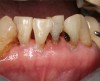

Fig 6. Use of 38% SDF to arrest root caries in permanent teeth of an elderly patient: the arrested root carious lesions were hard to probe.

Figure 6

Fig 7. Use of 38% SDF to arrest root caries in permanent teeth of an elderly patient: the lower incisors were responsive to electric pulp testing with no radiographic pathology.

Figure 7